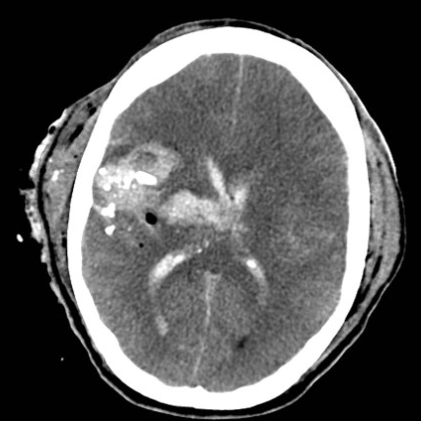

A 23 year-old man presents to the emergency department after an intoxicated fall and head injury. He has a moderate occipital headache and nausea without vomiting. On exam, the patient has normal vital signs and no focal neurological deficits. His non-contrast head CT is shown (Figure 1). The volume of the hematoma is measured to be 35 cm3. What is the most appropriate treatment for this patient?

A 24 year-old man is brought to the emergency department following a single midline gunshot wound to the forehead. On arrival, he is GCS 7T with bilateral sluggishly reactive pupils and localizing in the left upper extremity to noxious stimulus. His non-contrast head CT is depicted (Figure 1). This patient is most at risk for what acute complication of penetrating brain injury? Arteriovenous malformation Traumatic intracranial aneurysm Venous sinus thrombosis Traumatic arterial dissection Cavernous-carotid fistula

The correct answer is traumatic intracranial aneurysm. These lesions may develop along any artery within the pathway of the penetrating foreign body and may increase in size or rupture with significant morbidity and mortality. Although cavernous-carotid fistula and arterial dissection may occur in both blunt and penetrating trauma, **traumatic pseudoaneurysms are more concerning in penetrating trauma**. Venous sinus thrombosis may be present after venous injury, but an arterovenous malformation would be an incidental finding.

A 21 year-old-man sustained blunt force trauma to his head, had brief loss-of-consciousness and was GCS 15 at initial evaluation, complaining of headaches, nausea and visual disturbance. CT is shown in figures. What is the best management of this patient? Evacuation of hematoma with placement of burr holes Cerebral angiogram and embolization of sinus Place ICP monitor and observe in the ICU Manage conservatively in the ICU with a f/u CT in 6 hrs. Take to the OR emergently for a combined Supra- and infratentorial approach

Take to the OR emergently for a combined Supra- and infratentorial approach